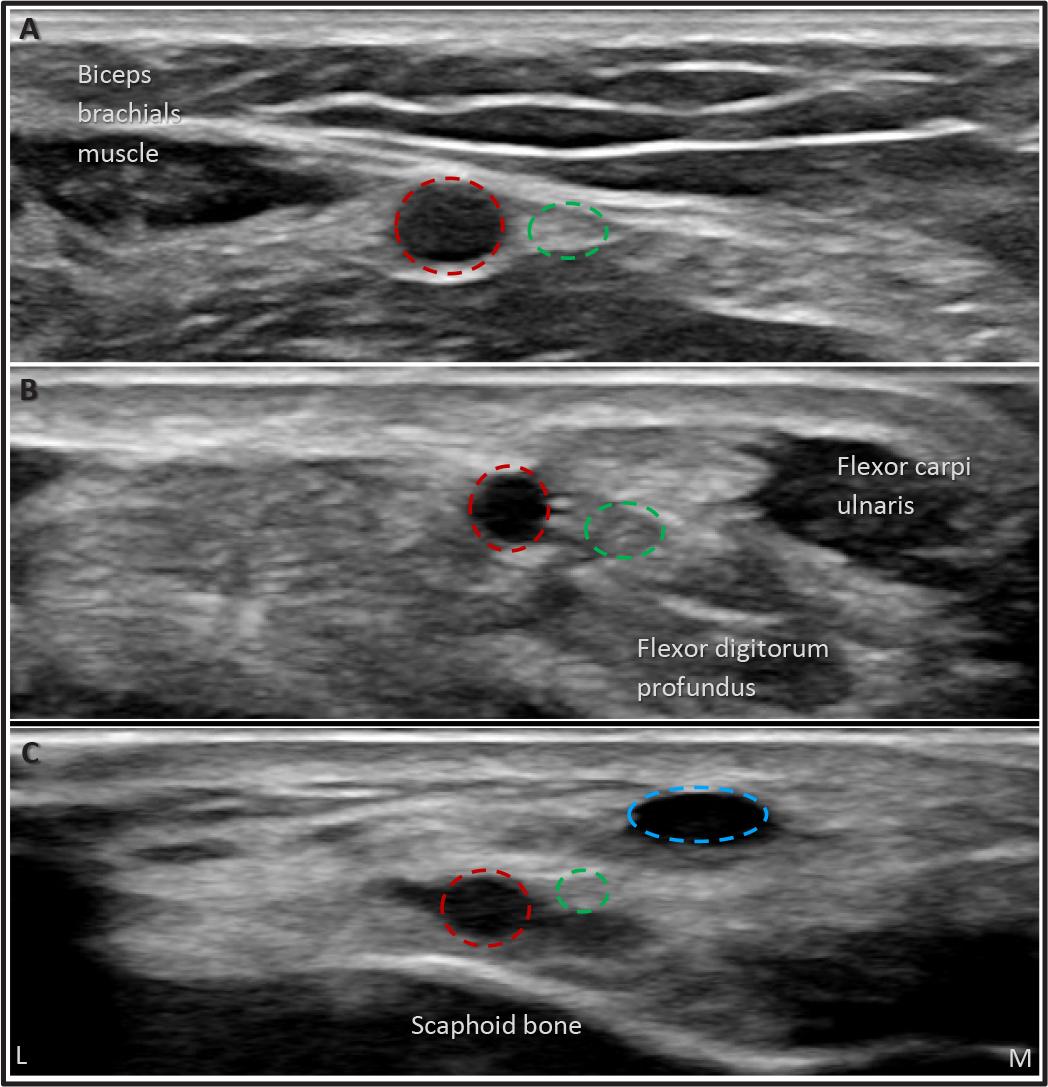

Ultrasound makes it easy to identify the scaphoid floor, extensor pollicis longus, and extensor pollicis brevis, accurately locating the distal radial artery and the optimal puncture site in a non-angulated segment, thus avoiding multiple punctures (Figure 2). Additionally, ultrasound allows the operator to measure the arterial diameter, ensuring appropriate sizing for the planned or potentially needed intervention.

Angulated segment of the distal radial artery which should be avoided during puncture. Blue dotted circle, cephalic vein.

A detailed ultrasound (US) analysis of the surrounding structures is recommended to select the optimal puncture site for distal radial access (DRA). The ideal site should be chosen based on several factors. First, the distance between the skin and the artery should be minimized to ensure the most superficial trajectory possible, facilitating easy access. Additionally, the DRA should be positioned close to a bone structure to secure effective compression and facilitate anastomosis. It is crucial to screen the surrounding structures to avoid puncturing the cephalic vein, superficial branches of the radial nerve, and, most importantly, the extensor tendons. Lastly, evaluating the tortuosity of the artery and visualizing its curvilinear trajectory in the long axis can help select the most suitable puncture site (Figure 2).